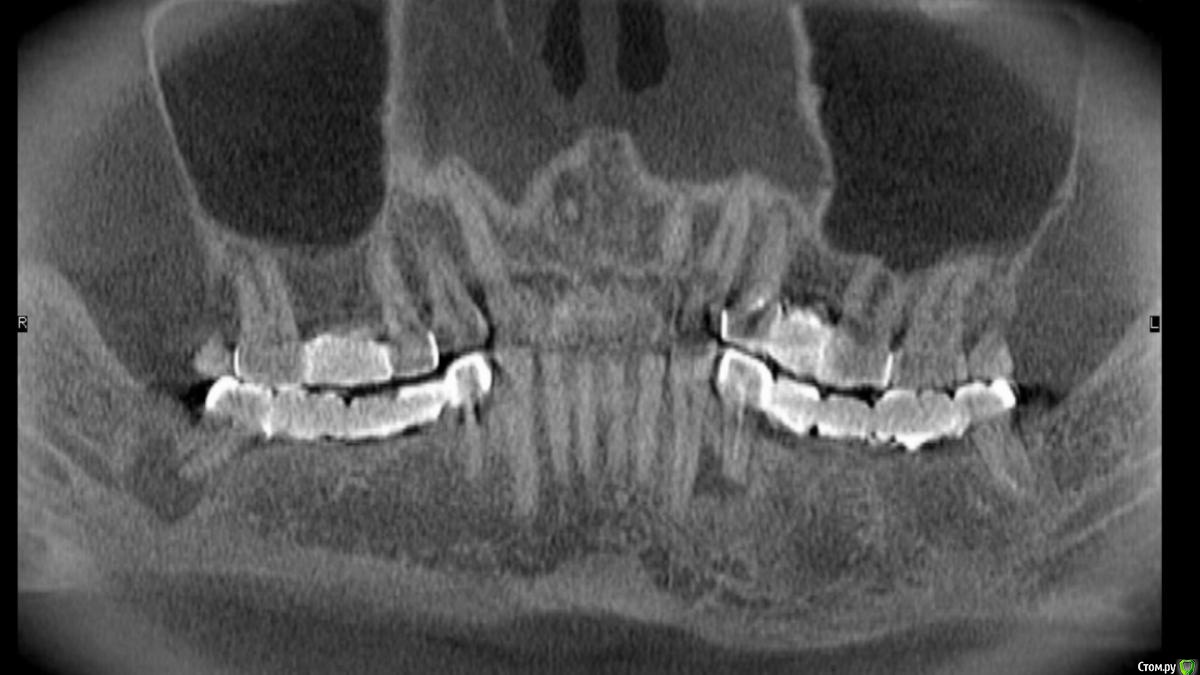

Foxtrot Опубликовано 27 мая, 2018 Поделиться Опубликовано 27 мая, 2018 Здравствуйте, коллеги. Пациент М 49 лет, планируется удаление зубов: 47, 44, 34 и установка 6-ти имплантов на н/ч. Смущает ситуация в области 34;44. Стоит ли идти на одномоментную имплантацию или лучше удалить и подождать? Ссылка на комментарий